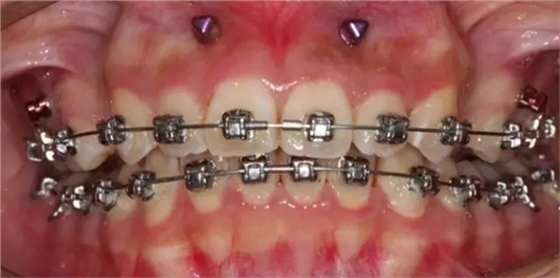

上下牙列擁擠,磨牙尖牙Ⅱ 類關(guān)系,3 度的深覆牙合,上頜中切牙伸長內(nèi)傾拔除上頜雙側(cè)的第一前磨牙,先粘上頜高轉(zhuǎn)矩的自鎖托槽排齊牙列,唇向開展上頜切牙,有一定的覆蓋,粘下頜標準轉(zhuǎn)矩托槽,上頜 1, 2 之間植入種植支抗壓入,同時后牙 5, 6 之間植入種植支抗內(nèi)收前牙,打開咬合關(guān)閉間隙。治療關(guān)鍵:前牙轉(zhuǎn)矩的控制第 1 個月 上頜粘上 Damon Q 高轉(zhuǎn)矩托槽,上 .014 熱激活 NiTi 絲。第 3 個月 上換 .014 x .025 熱激活 NiTi 絲。第 5 個月 上頜基本排齊,覆蓋增大,上換 .017 x .025 NiTi絲,下頜粘托槽,下 .014 熱激活 NiTi 絲。第 7 個月 上 .017 x .025 NiTi 絲加搖椅,下?lián)Q .014 x .025 熱激活 NiTi 絲第 9 個月 上頜換 .019 x .025 NiTi 絲加搖椅,下頜換 .017 x .025 NiTi 絲第 11 個月 下頜換 .019 x .025 加搖椅,上頜 1, 2 之間, 5, 6 之間植入種植釘,下頜出現(xiàn)散隙。第 13 個月 上頜換 .019 x .025ss 加搖椅,前牙種植釘用 Power Chain 壓低前牙(每側(cè) 100g),后牙種植釘關(guān)閉間隙(每側(cè) 150g),下?lián)Q .019 x .025ss,Power Chain 關(guān)閉間隙。第 19 個月 上頜前牙基本壓低到位去除前牙種植釘,繼續(xù)用關(guān)閉間隙,下頜散隙關(guān)閉。